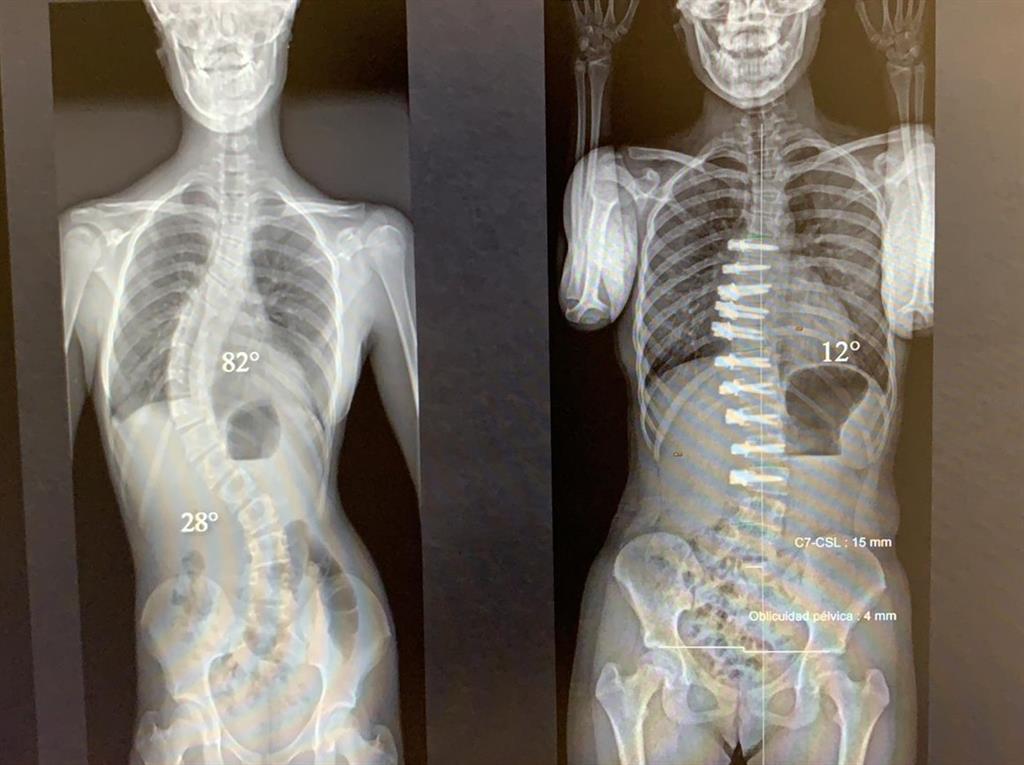

Cuanto Cuesta Una Operacion De Escoliosis En España, , , , , , , 0, FOTOGALERÍA| Realizan histórica cirugía de escoliosis en SLP, pulsoslp.com.mx, 1280 x 1280, jpeg, Webactualizado 3/8/2023. El precio promedio del diagnóstico y tratamiento de Escoliosis en España es de $7500, el precio mínimo es de $6000, y el precio máximo es de. Web¿Cuánto cuesta una cirugía de escoliosis en México? El costo de operación de escoliosis en México puede oscilar entre los $200,000 mxn, dependiendo del., 20, cuanto-cuesta-una-operacion-de-escoliosis-en-espana, Novedades y Muebles Webactualizado 3/8/2023. El precio promedio del diagnóstico y tratamiento de Escoliosis en España es de $7500, el precio mínimo es de $6000, y el precio máximo es de. Web¿Cuánto cuesta una cirugía de escoliosis en México? El costo de operación de escoliosis en México puede oscilar entre los $200,000 mxn, dependiendo del.

WebPor lo general, la variabilidad que tiene que ver con el tipo de intervención que se haga no tiene por qué superar los 1.000 €. Es decir, si una otoplastia sencilla puede costar de. WebCuánto cuesta una operación de pecho. Según detallan las Clínicas Love, especializadas en cirugía estética, una operación de pecho en España ronda los 5.000. WebEn el Centro de Corrección de Escoliosis, la misma reducción tendría un costo de $8,500/19 = $447.36 dólares por grado. Esto es claro, sin tomar en consideración el peligro. WebHola buenas. Me gustaría saber, ya sea en la sanidad pública (que supongo que el costo es con cargo a los presupuestos pertinentes) o en la privada (costeándoselo. Web20.500 €. Neurocirugía, Cirugía de Columna. Hospitalización media. Media de gastos totales*. Fusión lumbar de columna (1 segmento) 3 noches. 28.000 €. Fusión lumbar de.